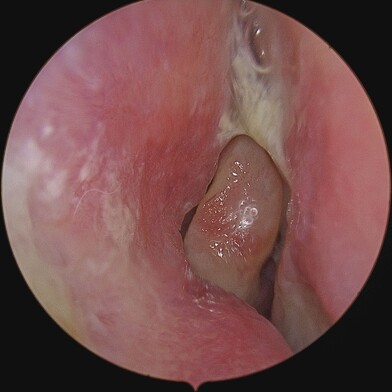

On the other hand, Chronic Sinusitis / Rhinosinusitis (CRS) is an inflammation and swelling of the sinus lining lasting longer than 12 weeks, often associated with persistent symptoms despite treatment. It can be caused by infections (bacterial / viral / fungal), allergies, environmental irritants like pollutants, anatomical abnormalities (e.g. nasal polyps) or autoimmunological factors. Patients with CRS display symptoms associated with the acute type along with headaches, a diminished sense or loss of smell (Hyposmia or Anosmia), or post-nasal drip.

Diagnosing chronic rhinosinusitis involves a comprehensive evaluation, which may include medical history and physical examination, nasal endoscopy, imaging studies, allergy testing, and conducting nasal and sinus cultures.